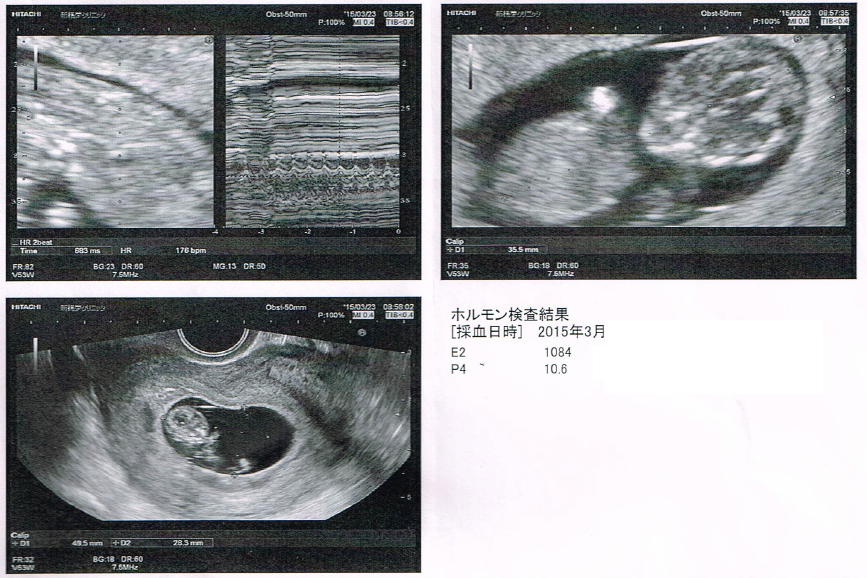

· bt17胎嚢確認診察。大きさやe2が平均値より低いのが気がかり。 18年3月21日 ホルモン補充移植周期bt22の「成長・ホルモン値評価」に行ってきました。 nacのプリントによると、週数は5w6d。 (bt22診察は、経過により診察なしの方もいるようです) 前回のbt17胎嚢確認で寺元先生が、 「次回心拍 · 平均5人が回答 50以上の診療科の医師 医師に相談する トップ カテゴリ一覧 妊娠・出産 高齢出産 5w1d,BT17の胎嚢の大きさについて close 無料公開について 会員限定Q&Aのうち、どなたでも医師回答を見られる直近14日間に投稿された相談です。 全250万件の本人認証済みの医師が答えるQ&Aは正常(平均27mm)と 流産(平均26mm)であまり違いが見られません。統計的にも違いなし。 つまり、5週0日までは胎嚢のサイズを気にする必要なし! 次に5週1日~6週0日(36日から42日)を見てください。 正常の平均mm、 流産の平均45mm。統計的にも違います。

胎嚢確認できて良かった という安心感はあったけれど、 なんとなく大きさが気になってネットで検索しちゃうとね、 女医先生は「順調」って言ってくれたけれど、 前も5W6Dで9.8mmの胎嚢が · BT17 胎嚢確認 5w1d まずは数値から↓ E2 2267 P4 06 βHCG この日、朝茶色い出血があり焦る。 茶色だけど出血は出血どきどきしながら病院へ行きました。 結果、HCGが驚きの伸びを見せてくれました! そして胎嚢も無事確認!サイズは58mmと小さめ。 ネットでいろいろ見てると大きさが心配になるものの、とりあえずホッとしました 出血については、茶色胎嚢は、62mmでした。 夢クリの基準値(BT17)が510mmとの事でしたので BT18の判定という事を考慮すると かなりギリギリの数値ではありますが (この時期胎嚢は1日1mm成長) 何とか基準値内はクリアしてくれました。 先生からは

0506 · BT17 胎嚢確認 アラサー主婦の妊活日記 (´ー`)NAC日本橋で顕微授精挑戦記録! 治療から妊娠に至るまで^^ 18年05月12日 1554 本日5w1dで、BT17の診察へ行ってきましたひとつ前の記事を見ていただくと分かりますが、今日までかなり気分が落ちた状態でした1507 · つわりのはじまり〜5週後半から つわり対策 記事一覧 KLC 2回目の判定日 BT7 0715 KLC BT17 胎嚢確認 →卒業なるか? ! テーマ: 妊活 ∴‥‥∴‥∵‥∴‥∴‥∵‥∴‥∵‥∴‥∴‥∵‥∴‥∵‥∴‥∴‥∵‥ *妊活記録* タイミング法→複数回 平成30年7月 人 · 胎嚢:最小92mm 最大249mm 胎芽:最小17mm(確認できないケースを除く) 最大69mm 自然妊娠の場合は、1名除き全員が胎嚢の大きさ10mm以上という結果になりました。 mm超えも9名います。